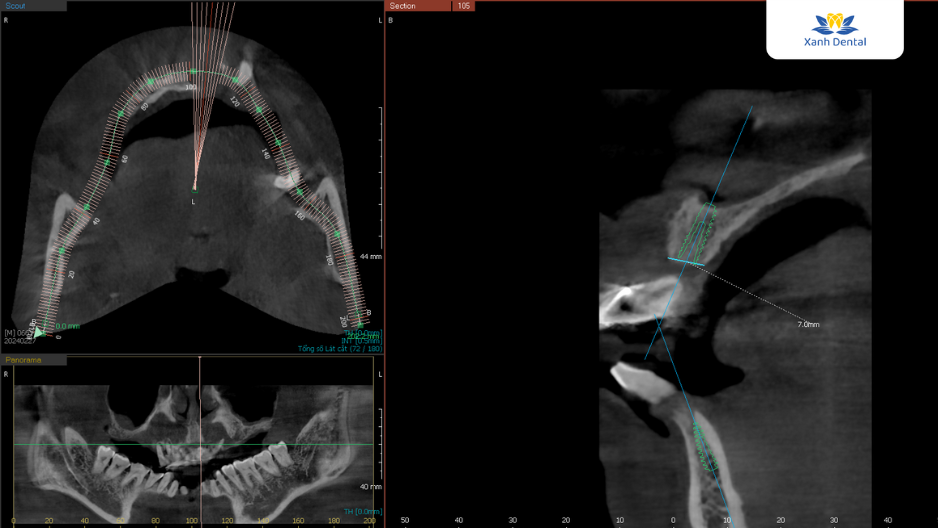

Sau khi thăm khám kỹ lưỡng và đánh giá tình trạng răng miệng của chú Sơn, Thạc sĩ, Bác sĩ Nguyễn Anh Sơn – chuyên gia cấy ghép Implant với hơn 5.000 ca điều trị thành công – đã xây dựng một phác đồ điều trị chi tiết và cá nhân hóa.

Kế hoạch cụ thể bao gồm cấy ghép toàn bộ hàm răng trên bằng phương pháp All-on-4 Implant và cấy 4 trụ Implant khôi phục lại răng cửa hàm dưới. Đây là phương pháp tiên tiến giúp thay thế chân răng đã mất bằng trụ Implant Titanium, mang lại khả năng ăn nhai và thẩm mỹ gần như răng thật. Cùng với công nghệ hiện đại, việc cấy ghép diễn ra nhẹ nhàng, không đau và đảm bảo an toàn tuyệt đối. Đặc biệt, răng sứ được phục hình trên trụ Implant có màu sắc tự nhiên, mang lại tính thẩm mỹ tối đa cho khách hàng.